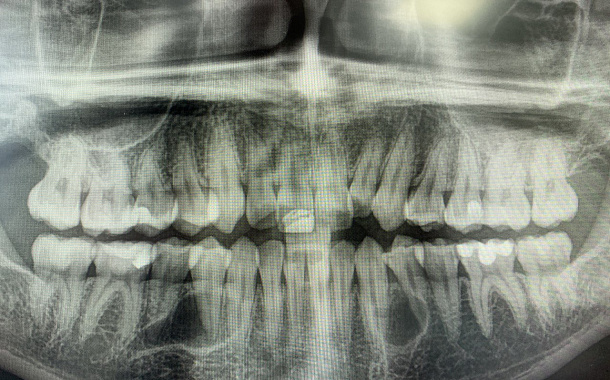

Удаление зуба — исключительная процедура, которая выполняется строго по медицинским показаниям. Если есть хоть малейший шанс спасти зуб, в Немецком Стоматологическом Центре всегда идут по пути сохранения зуба. Перед плановым удалением, проводится тщательная диагностика и оценка состоятельности корня разрушенного зуба, возможность его эндодонтического лечения и последующего восстановления. Диагностика включает:

• компьютерную томографию. Обследование в формате 3D на томографе дает полную картину состояния зубочелюстной системы, что очень важно для грамотного планирования удаления.

Перед операцией обязательно проводится предварительная рентгенологическая, визуальная, инструментальная диагностика, на основании которой врач определяет тактику дальнейшего лечения.

Сложное анатомическое расположение и анатомия самих зубов, близкое расположение важных анатомических образований (нижнечелюстной канал, гайморова пазуха) и их взаимосвязанное расположение с корнями «восьмых» зубов, требует от врача-хирурга тщательного анализа клинической ситуации, данных 3D рентгенографии и оценки всех возможных рисков и осложнений, как во время операции, так и после ее проведения.